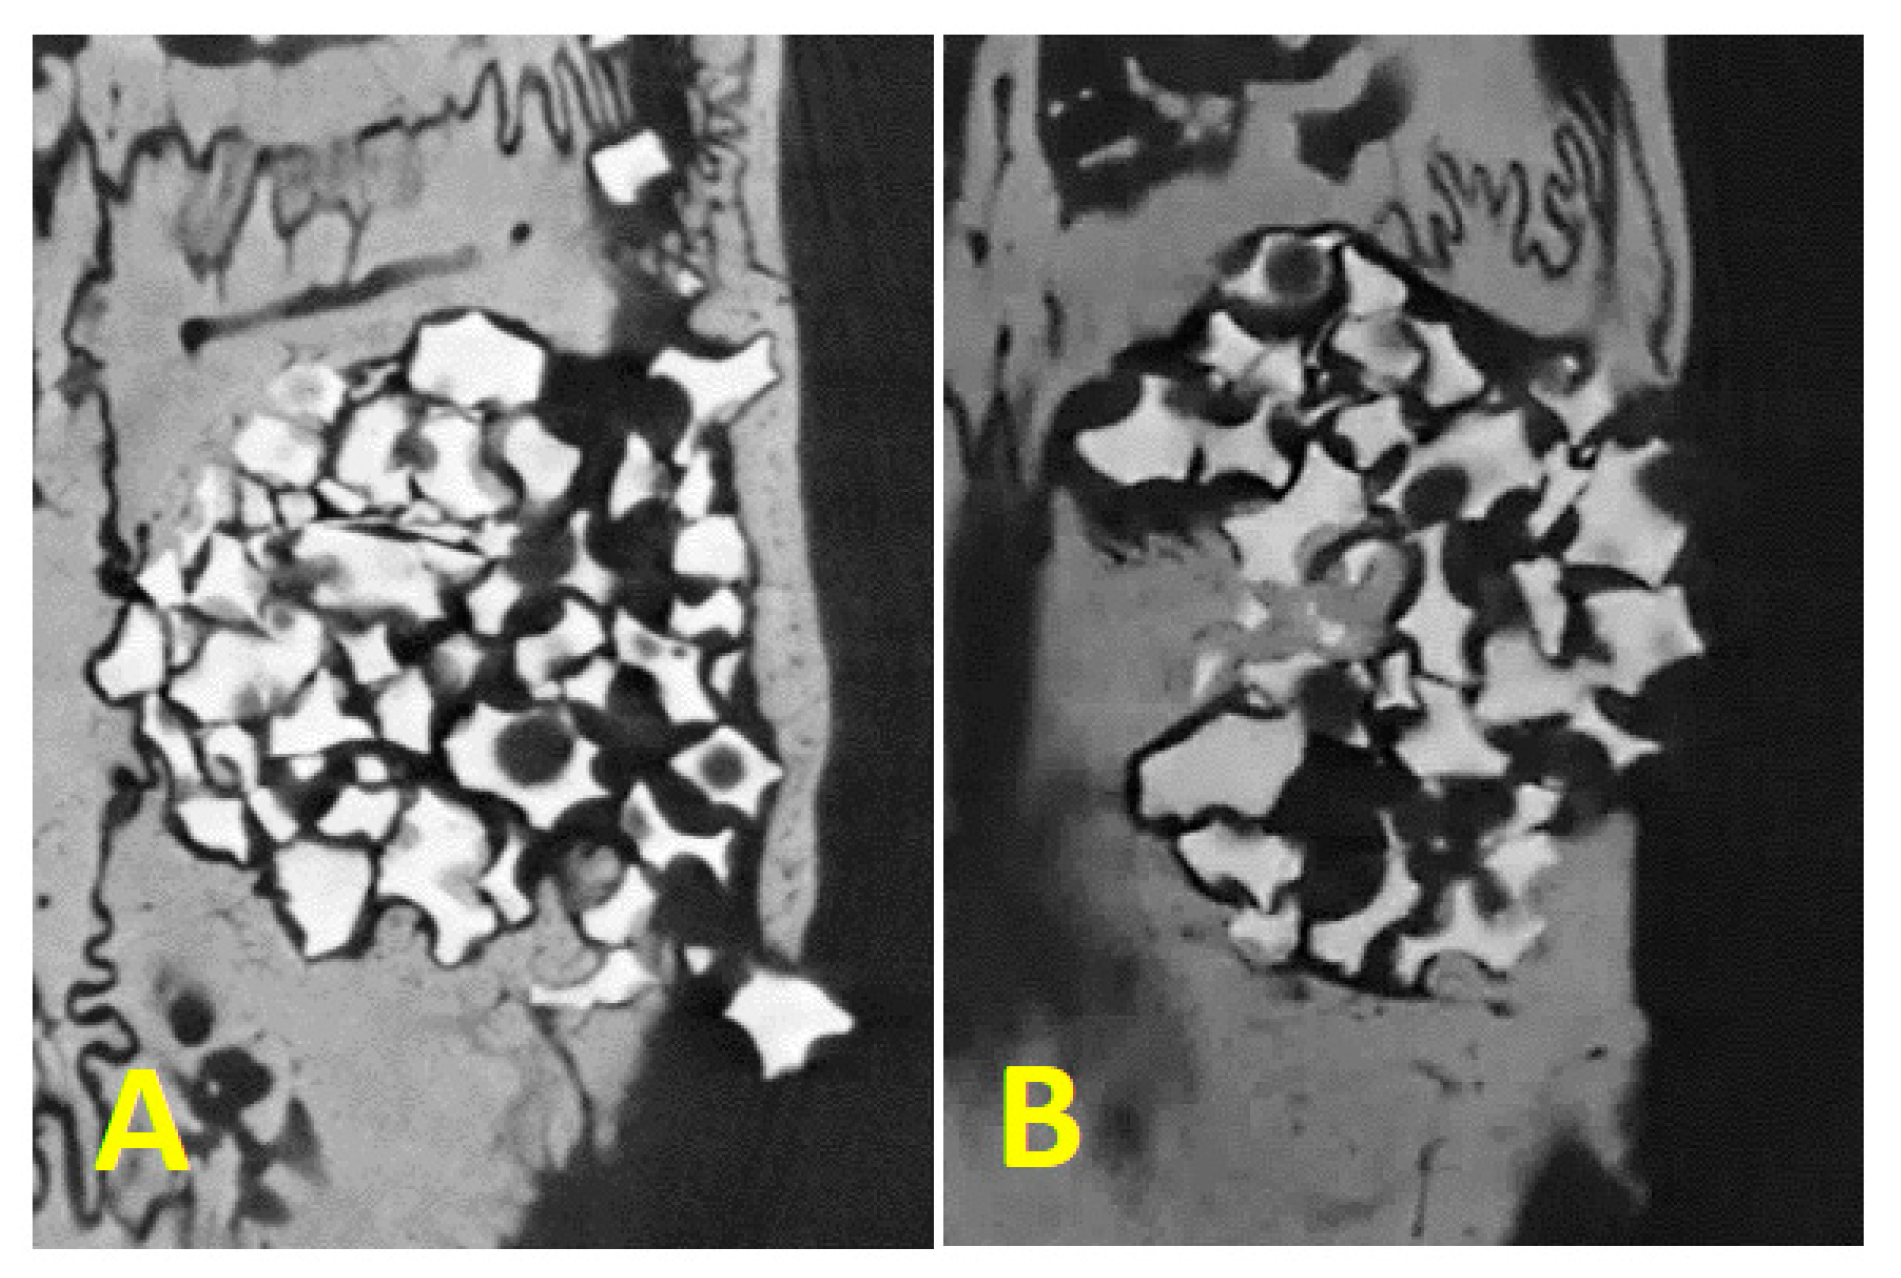

3.4. Micro-CT Analysis